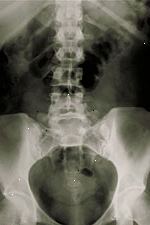

Οσφυϊκή X-ray

Ενώ η ίδια η διαδικασία ακτίνων Χ δεν προκαλεί πόνο, ο χειρισμός του μέρους του σώματος που εξετάζεται μπορεί να προκαλέσει κάποια δυσφορία ή πόνο, ιδιαίτερα στην περίπτωση μιας πρόσφατης τραυματισμό ή επεμβατική διαδικασία, όπως η χειρουργική επέμβαση. Ο τεχνολόγος ακτινολογικές θα χρησιμοποιήσει όλα τα δυνατά μέτρα για την άνεση και την ολοκλήρωση της διαδικασίας το συντομότερο δυνατόν για να ελαχιστοποιηθεί οποιαδήποτε δυσφορία ή πόνο.